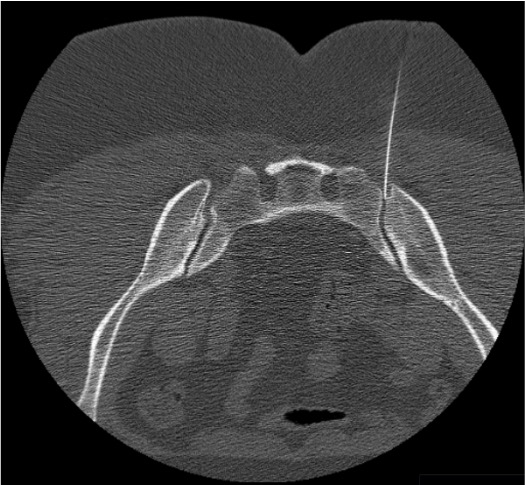

- CT guidance: Preferred when ankylosis is present (ankylosing spondylitis) or when the joint is not well visualized fluoroscopically. Allows direct visualization of needle tip in the joint space.

- Ipsilateral oblique (15–25°): Separates the joint into a single clear lucent line. The inferior portion is most accessible. This is the primary working view for needle advancement.

- Fluoroscopic challenge: oblique joint orientation + overlapping iliac and sacral cortices → ipsilateral oblique view mandatory to separate joint lines